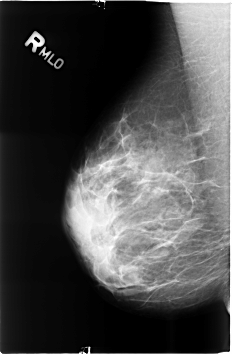

ics_version 1.0 filename B-3497-1 DATE_OF_STUDY 20 5 1998 PATIENT_AGE 38 FILM FILM_TYPE REGULAR DENSITY 3 DATE_DIGITIZED 8 6 1999 DIGITIZER LUMISYS LASER SEQUENCE LEFT_CC LINES 4624 PIXELS_PER_LINE 3056 BITS_PER_PIXEL 12 RESOLUTION 50 OVERLAY LEFT_MLO LINES 4640 PIXELS_PER_LINE 3072 BITS_PER_PIXEL 12 RESOLUTION 50 OVERLAY RIGHT_CC LINES 4600 PIXELS_PER_LINE 3032 BITS_PER_PIXEL 12 RESOLUTION 50 NON_OVERLAY RIGHT_MLO LINES 4600 PIXELS_PER_LINE 3008 BITS_PER_PIXEL 12 RESOLUTION 50 NON_OVERLAY |